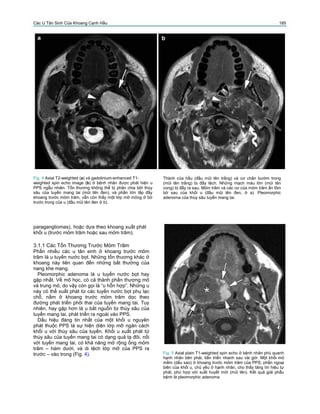

Fig. 6 Axial T2-weighted spin echo images (a–c) ở bệnh nhân

vào viện vì phù phía dưới tai, 9 năm sau phẫu thuật vì

pleomorphic adenoma. Nhiều tổn thương dạng nốt sáng (mũi

tên), nằm ở phần nông và phần sâu của cơ ức đòn chũm và cả

khoang trước mỏm trâm của PPS (mũi tên, c). Phẫu thuật lại

cho kết quả là pleomorphic adenoma tái phát

Fig. 7 Bệnh nhân khoảng 50 tuổi, tiền căn có pleomorphic

adenoma ở thùy sâu của tuyến mang tai. Sau lần phẫu thuật

đầu tiên, u tái phát được cắt cách đây khoảng 1 năm. Hiện tại

bệnh nhân vào viện vì đau quanh tai và cứng hàm, và một

khối u ở vùng trước tai và dưới hàm. CT cho thấy một khối

tổn thương lớn ở khoang tuyến mang tai, khoang trước và

sau mỏm trâm của PPS (mũi tên, a), lan rộng vào khoang nhai

và khoang mút (đầu mũi tên, a), và vào sàn miệng, và vùng

quanh tĩnh mạch cảnh và vùng dưới hàm (mũi tên, b).

Có thể thấy hủy xương lan rộng của thân xương hàm dưới bên

trái (đầu mũi tên, b). Vài hạch bệnh lý nhóm II bên trái. Những

lát cắt CT ở thấp hơn cho thấy di căn phổi. Mặc dù những lần

sinh thiết lại đều là pleomorphic adenoma, biểu hiện lâm sàng

và hình ảnh phù hợp với khối u hóa ác. Bệnh nhân được hóa

trị hỗ trợ và bệnh nhân tử vong sau 1 năm do ung thư tiến

triển.

Mặc dù pleomorphic adenoma là u lành tính, u có

thể tái phát tại chỗ nếu cắt u, do tổn thương có vỏ

bao mỏng không hoàn toàn. Thường gặp những tổn

thương tái phát đa ổ và có tín hiệu rất cao trên các

xung T2 (Fig. 6).

Chuyển dạng ác tính của thành phần thượng mô

của pleomorphic adenoma, được gọi là ‘carcinoma

ex pleomorphic adenoma’ hoặc ‘malignant mixed

tumor’, là nguyên nhân chính để cắt bỏ hoàn toàn

pleomorphic adenomas. Biểu hiện lâm sàng là tăng kích

thước khối u đột ngột, đôi khi đi kèm đau và liệt dây

thần kinh. Biểu hiện hình ảnh đôi khi tương đối khó

phân biệt giữa “lành tính” và “ác tính”, hoặc tổn thương

có thể xâm lấn và phá hủy những cấu trúc xung quanh

(Fig. 7).